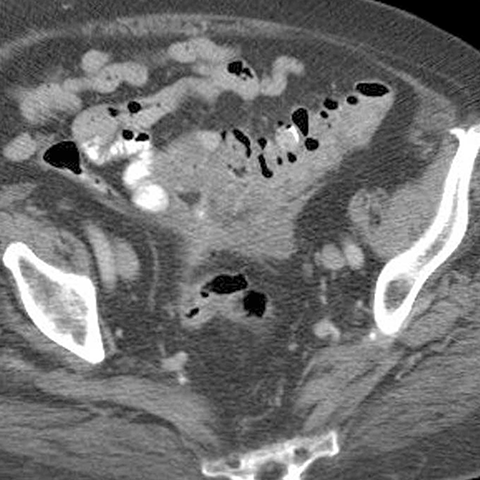

65 year-old male presents with fever and LLQ pain. [3 of 5]